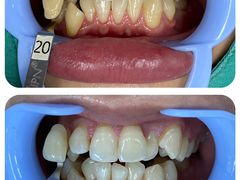

• 同步齿科·同富门诊·正畸种植口腔旗舰店(布吉店)

• -同步齿科·同富门诊·正畸种植口腔旗舰店(布吉店)

Kafutree | 23-11-13

报错